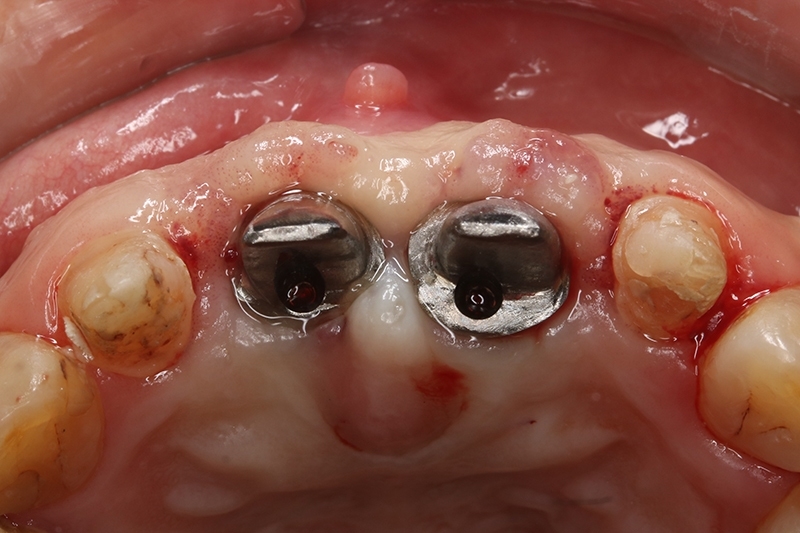

接續牙周治療完成後的療程,上排門牙植牙的問題處理,長期不斷的發炎化膿流血,除了造成周圍組織發炎與牙齦腫脹,同時造成齒槽骨被細菌破壞與吸收,根本解決的方式是建議移除感染與位置不佳的植體,先進行植牙移除手術+齒槽骨保存術,先使用膠原蛋白促進軟組織癒合,加快癒合的速度。

可見植體移除後骨缺損範圍大

取出的舊有one piece植體,舊式植體。

初步等待2個月軟組織癒合,再來進行垂直脊水平骨牙脊增寬術,使用不可吸收再生膜Cytoplast 及迷你骨釘 Tack固定放置的人工骨粉。

明顯看到水平骨頭缺損範圍

垂直骨頭缺損情況